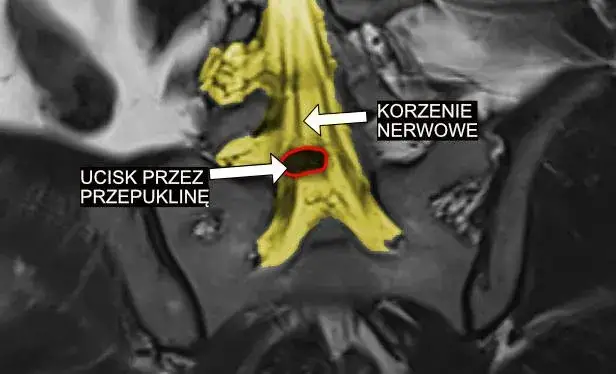

Poznaj skuteczne metody leczenia schorzeń korzeni rdzeniowych i splotów nerwowych w Polsce. Od farmakoterapii po operacje. Odkryj kompleksowy przewodnik.